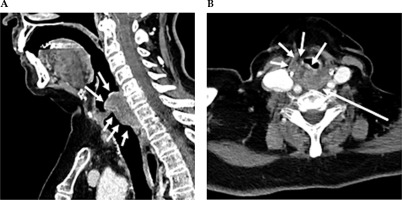

Fig. 1

Contrast-enhanced CT neck scan demonstrating malignancy of the hypopharynx. A) Sagittal view and B) axial view. A) Sagittal CT imaging shows enhancing infiltrating soft tissue thickening, along with the post-cricoid posterior hypopharyngeal wall, with extension above and below the vocal cords. B) Axial CT imaging shows that at the level of the false vocal cords, there is heterogeneously enhancing bulky soft tissue in the posterior hypopharyngeal wall, with extension and infiltration into the paraglottic fat anteriorly